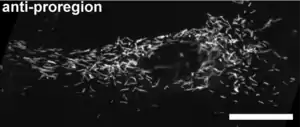

Los cuerpos de Weibel-Palade (WPB) nacen en la Red del trans Golgi donde brotan en forma de estructuras discernibles. Sus dimensiones y morfología únicas, están dictadas por la carga principal el factor VWF, una glucoproteína grande. Luego, el factor VWF se transporta al Golgi donde se ensambla en cuantos definidos.

Hay dos componentes principales almacenados en los cuerpos de Weibel-Palade. El primero es el factor de von Willebrand (vWF), una proteína multimérica de gran importancia en el proceso de coagulación de la sangre.[3]